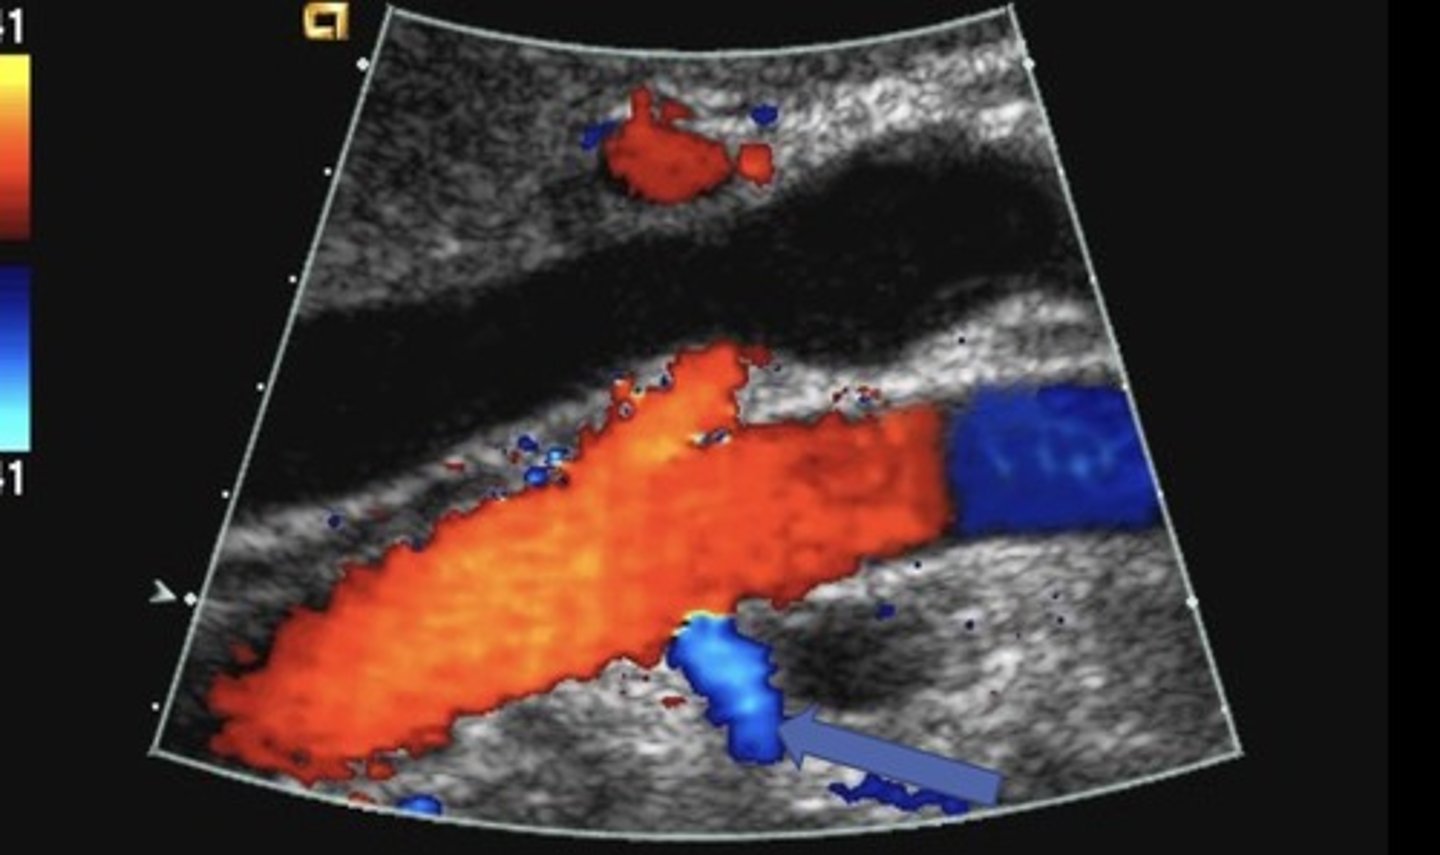

Cavernous Transformation

Due to chronic portal vein thrombosis

Occurs within 6 days after thrombotic event

Absent portal vein flow

Formation of new peri-portal vessels around portal vein

Hepatopetal flow within serpentine vessels